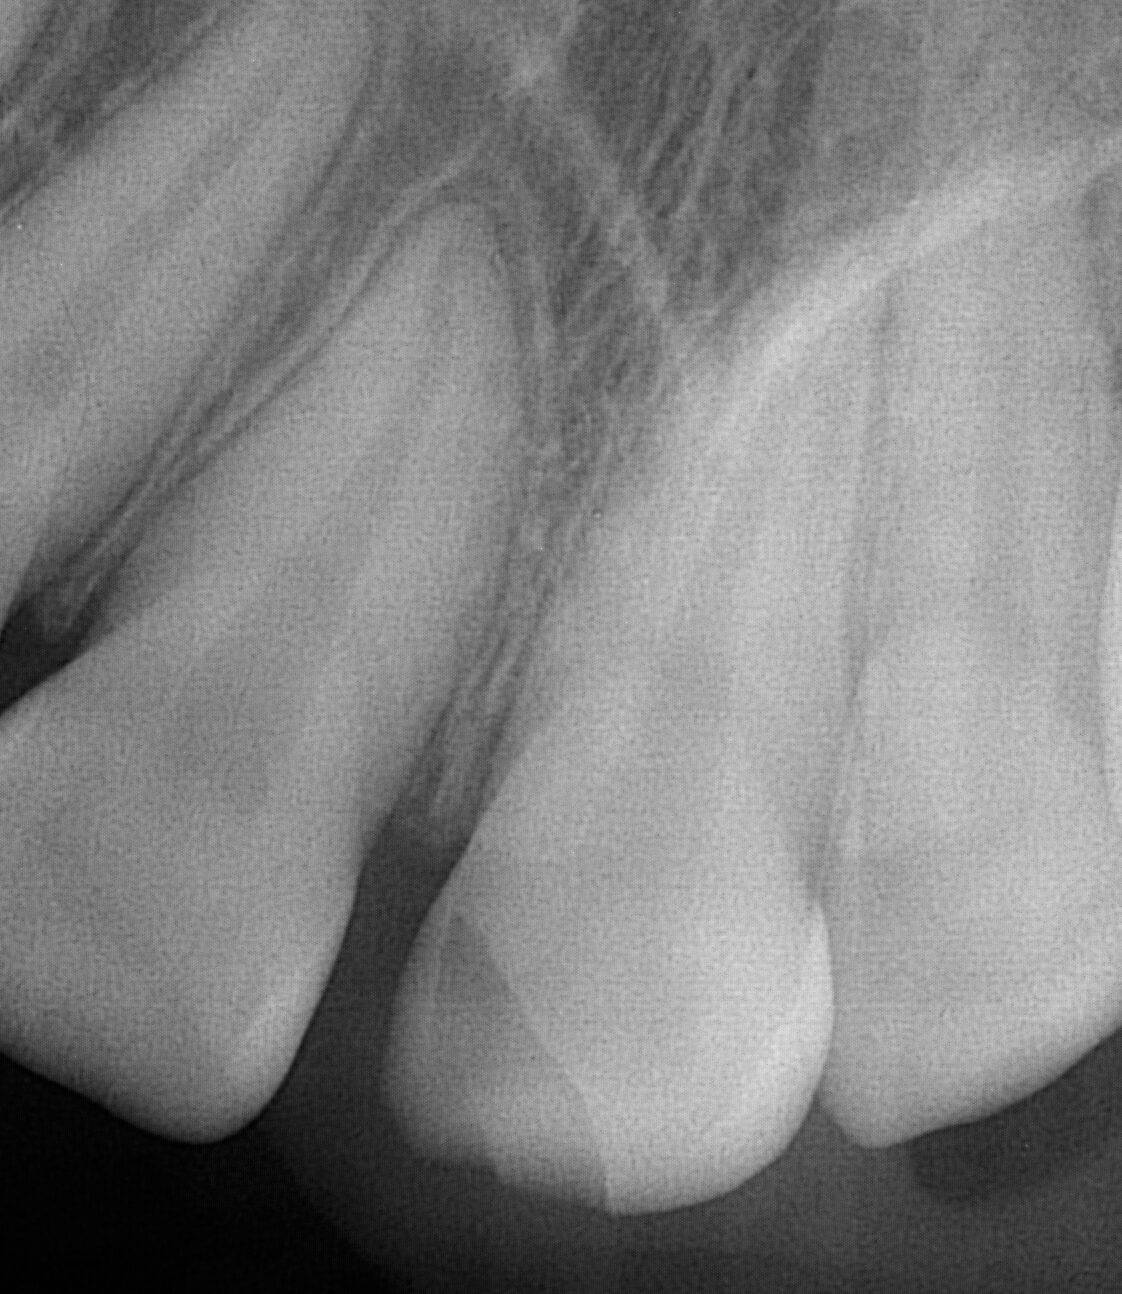

12 year old male patient fell of his bicycle on a Saturday. He hit his lip and front teeth on the pavement. He did not have much tooth pain after the initial trauma. He presented the next day to our office to evaluate the tooth for repair. As an emergency dentist in NYC we treat all types of tooth injuries.

Luckily, his front tooth did not suffer any nerve damage. The tooth was not mobile and mostly intact aside from the obvious fracture. The nerve in the tooth is was healthy, not causing any significant pain.

Since the front tooth did not sustain any nerve damage it was safe to proceed with restoring the tooth with a bonding. A bonding is the same material we often use in dental fillings. We usually do not place porcelain veneers or crowns on patients under 17 years old. Since, young patients’ bone is still growing, the crown may not look correct a few years after placement.